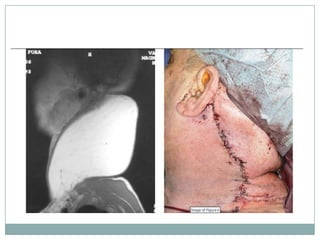

La aparición de lipomas gigantes a nivel cervical es

infrecuente. Es necesaria la realización de pruebas de

imagen para una correcta localización anatómica y

establecer relaciones con las estructuras vecinas.